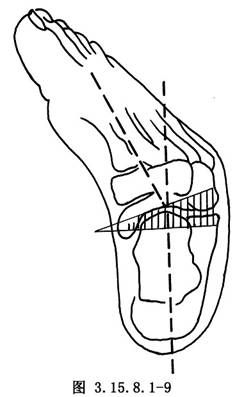

6.5.3 3.截骨矫形

先用骨刀截除跟骰关节和距舟关节,楔形截骨基底在背外侧纠正内翻畸形(图3.15.8.1-8),切除角度等于X线片第2趾和足中线形成的角度(图3.15.8.1-9)。若纠正足外翻畸形,楔形截骨基底可设计在内侧(图3.15.8.1-10),由于距舟关节和跟骰关节在一个平面上,切除角度是一致的(图3.15.8.1-11)。最后切除距下关节,纠正跟骨内收(图3.15.8.1-12),根据X线片胫骨中线和跟骨中线形成的角度,做外侧楔形切除(图3.15.8.1-13)。当骨刀切到对侧时,注意轻缓,尤其纠正外翻时,更要注意防止误伤胫后的血管及神经(图3.15.8.1-14)。将已切除的骨面合拢,如畸形纠正,骨面能紧密对合(图3.15.8.1-15),周围空隙植入切除多余的松质骨。